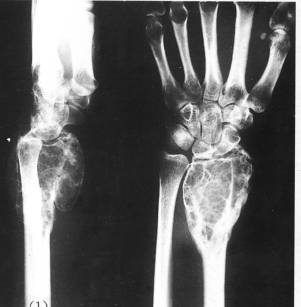

3)软骨瘤

①好发部位:40%--65%发生手部,特别是近节指骨最为多见

②好发年龄:30--40岁为好发年龄

③临床表现:患者多为无痛性肿胀,常并有病理性骨折,发生在躯干部的软骨瘤有恶变倾向

④治疗:手术治疗为主,采用刮除或病端切除植骨术,预后好